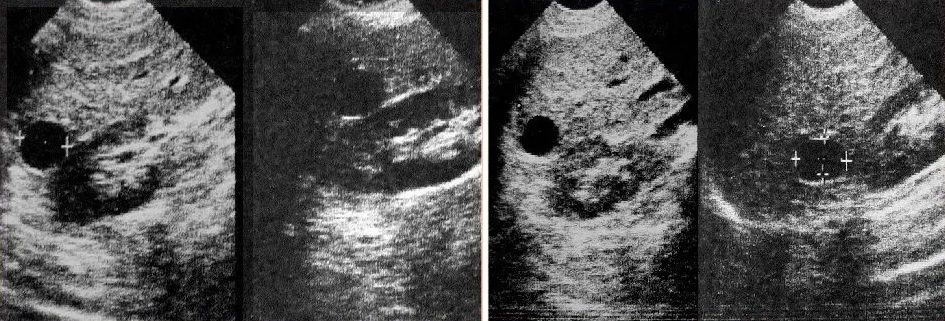

- УЗИ: в основе метода лежит отражение органом высокочастотных звуковых волн и построение изображений и видео внутренних структур в режиме реального времени;

При необходимости выполняют лабораторную диагностику (определение специфических антител к антигену эхинококковой инфекции в крови), УЗИ с контрастированием для усиления визуализации структур, кровотока, а также пункцию с последующим цитологическим исследованием.

Бессимптомные кисты размером до 4 см не нуждаются в лечении, но требуют наблюдения в динамике: УЗИ проводят с 3-12 месячным интервалом. При стабильном состоянии в течение трёх лет динамическое наблюдение прекращается.

- Чрескожная пункция под ультразвуковым контролем с последующим введением склерозирующего вещества — наиболее безопасный малоинвазивный метод. Иногда крупные кисты могут рецидивировать и требуют повторного дренирования.